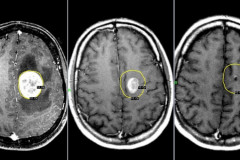

Գլխուղեղի ուռուցքի առաջին 10 նշանները, որոնց մասին պետք է յուրաքանչյուրն իմանա